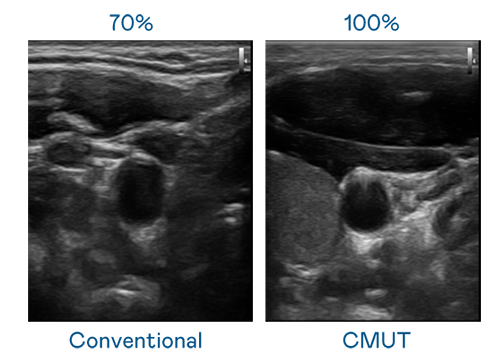

CMUT 技术是一种用电容式微机电元件来产生超音波讯号的技术。与传统 PZT 压电式技术相比,CMUT 频宽增加 30%,更宽频的超音波讯号让影像解析度大幅提升,是实现高影像品质医疗超音波扫描、促进精准医疗发展的关键技术。

大频宽带来超清晰影像

超音波影像的解析度高低,首先取决于探头能发出的讯号频宽。CA88 CMUT 可提供高清晰的超音波讯号,提供高频宽、高灵敏度、影像纹理细节更高的超音波影像,协助医护人员缩短影像判读时间及利用精准的医疗影像进行诊断。